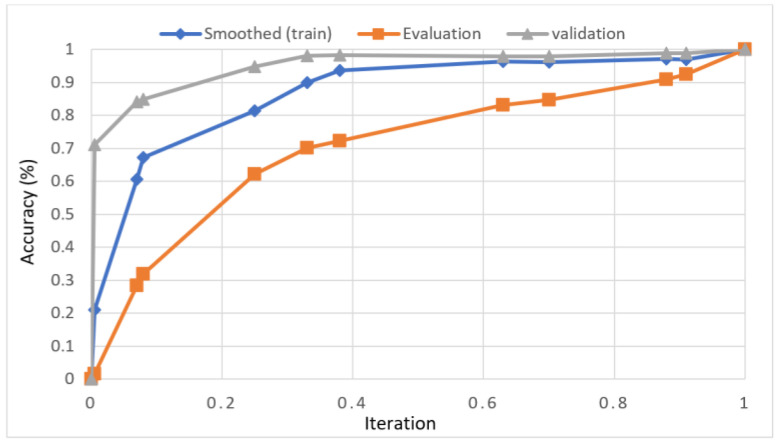

For knee RA severity classification, we conducted this research using a modified version of the VGG16 architecture and a domain adaptation technique, as shown in Figure 3. The VGG16 model was made up of five convolutional layers, three max-pooling layers, and three fully connected layers—all the digital X-radiation images needed to be resized to (227 × 227 × 3). In our implementation, X-radiation image information for training purposes accounted for eighty percent of the total, while X-radiation image information for evaluating purposes accounted for twenty percent. Although there are sixteen layers in VGG16, only a subset of those layers is required for feature extraction. In order to shorten the amount of time needed for training and establish more control over the fitting process, we assigned a dropout ratio value of 0.5 to the completely connected layer (fcl6) and the fully connected layer (fcl7). The characteristics were taken from the fully connected layers designated fcl6 and fcl7, respectively. To categorize the retrieved features into 1000 categories, VGG16’s architecture used a fully connected layer (fcl8). Then, we conducted one last round of tuning on the pre-trained VGG16 model’s ability to classify RA by changing parameters in the model’s last three layers. The model’s last three layers were swapped out for a fully linked layer, a softmax layer, and a classification layer. In addition, a newly linked layer was assigned to five groups of RA grades for the dataset: Grade 0, Grade 1, Grade 2, Grade 3, and Grade 4. We trained the proposed network by using digital knee X-radiations, a small-batch test dataset, gradient descent, and maximal epochs. Our proposed network learning strategy used stochastic gradient descent, and we compared its performance to previous efforts. The proportion of knee X-radiation images from the test set for which the network correctly predicted the RA grade was used to calculate proposed work accuracy. The proposed approach achieved an overall accuracy of 99.10% in classifying knee RA cases. Table 5 illustrates the Visual Geometry Group (VGG16) CNN operation for RA grade classification. Figure 4, depicts the RA classification using VGG16 architecture.

Sample images of the marginal joint space narrowing region of interest can be seen in Figure 5. The IoU (Intersection of Union) metrics were used to evaluate our region of interest detection system. This metric was the size of the intersection between the area of the actual bounding box and the area of the predicted bounding box divided by the size of the area of both boxes added together. When the IoU was 0.70, the narrow marginal joint space was found in 99.72% of the knee joints using our presented model. Additionally, Figure 6 depicts the ROC curve for marginal joint space narrow detection. The results of the presented marginal joint space narrow detection model obtained a sensitivity rate of 98.67%, a Dice score of 98.58%, a precision rate of 98.46%, a specificity rate of 98.50%, a false positive rate of 0.0100, a false negative rate of 0.0197, and an overall accuracy rate of 98.97%, as shown in Table 6, and the graphical illustration of Table 6 values is depicted in Figure 7. Table 7 demonstrates the metric performance outcomes of the proposed ResNet101 and VGG16 model to classify the RA. From Table 7, the outcome of the VGG16 outperforms the well-pre-trained ResNet101 model in classifying RA.

The presented model achieved 99.10% accuracy on the whole test set. The confusion matrix of the presented method is shown in Figure 8, and its performance is compared in detail to that of current methods in Table 5. In Figure 8, we examine the training and learning procedure as a whole to assess the planned activity’s success. Table 6 demonstrates the highest accuracy rate for classifying CBD grades zero–three–four knee joints. The knee joints with a CBD grade of one or two are the toughest to categorize. As can be seen in Figure 8, there is only a marginal amount of room for error when classifying knee joints as CBD Grades zero, three, or four. Knee joints that are classified as CBD Grades one or two have a small number of marginal misclassifications. In several circumstances, the proposed approach incorrectly estimated CBD Grade two as Grade one and vice versa. Joint space narrowing and bony spur development are significantly different in CBD Grade four knee joints. However, CBD-grade one knee joints show little change in JSN or osteophyte growth compared with the other classes. Types of knee RA and their intensity levels are shown in Figure 5. Table 8 and Figure 9 illustrate the JSN accuracy of the proposed and other state-of-the-art methods comparison.

In this study, we developed a deep learning model to automatically grade the severity of knee RA using a consensus-based approach. We compared the proposed work to prior strategies and found that it outperformed the competition. At the elementary level, notably in Grade one and Grade two, we found that our method differed from that of the medical professionals. We evaluated the presented work by comparing its results with similar existing studies. Compared with previously existing models, the presented work (a knee joint space narrowing diagnosis and class label) fares very well. It takes about 7 h of training to reach 0.6 k iterations. The outcomes of the presented methodology are shown in Table 9, which includes the outcomes of each CBD grade individually. Multiple metrics were employed to estimate the model’s performance, as indicated in Table 10. Figure 10 and Figure 11 depict the ROI curve for RA severity classification for both knees.